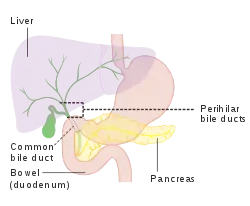

The biliary tract (also biliary tree or biliary system) refers to the liver, gallbladder and bile ducts, and how they work together to make, store and secrete bile.[1] Bile consists of water, electrolytes, bile acids, cholesterol, phospholipids and conjugated bilirubin.[2] Some components are synthesized by hepatocytes (liver cells); the rest are extracted from the blood by the liver.[3]

Bile is secreted by the liver into small ducts that join to form the common hepatic duct.[4] Between meals, secreted bile is stored in the gallbladder.[5] During a meal, the bile is secreted into the duodenum (part of the small intestine) to rid the body of waste stored in the bile as well as aid in the absorption of dietary fats and oils.[5]

The biliary tract refers to the path by which bile is secreted by the liver then transported to the duodenum, the first part of the small intestine. A structure common to most members of the mammal family, the biliary tract is often referred to as a tree because it begins with many small branches that end in the common bile duct, sometimes referred to as the trunk of the biliary tree. The duct, the branches of the hepatic artery, and the portal vein form the central axis of the portal triad.[7] Bile flows in the direction opposite to that of the blood present in the other two channels.[8]

The system is usually referred to as the biliary tract or system,[9] and can include the use of the term "hepatobiliary" when used to refer just to the liver and bile ducts.[1] The name biliary tract is used to refer to all of the ducts, structures and organs involved in the production, storage and secretion of bile.[10]

The tract is as follows:

- Bile canaliculi >> Canals of Hering >> intrahepatic bile ductule (in portal tracts / triads) >> interlobular bile ducts >> left and right hepatic ducts[4]

- These merge to form the common hepatic duct[4]

- The common hepatic duct exits the liver and joins with the cystic duct from gall bladder[4]

- Together these form the common bile duct which joins the pancreatic duct[4]

- These pass through the ampulla of Vater and enter the duodenum[4]